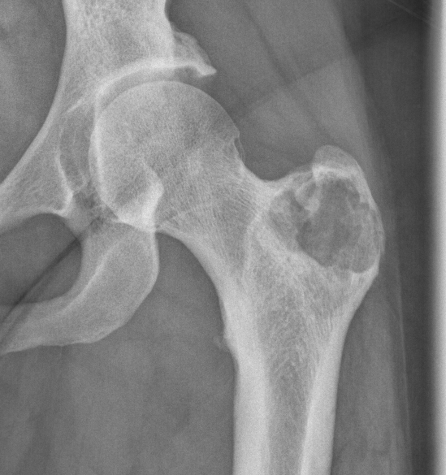

X-ray

Well defined eccentrically located epiphyseal lesion

- thin sclerotic reactive rim

- may have calcification

Femoral head osteoblastoma

- 14 cases

- open dislocation and modified trapdoor approach

- no local recurrence

- one case AVN requiring joint replacement